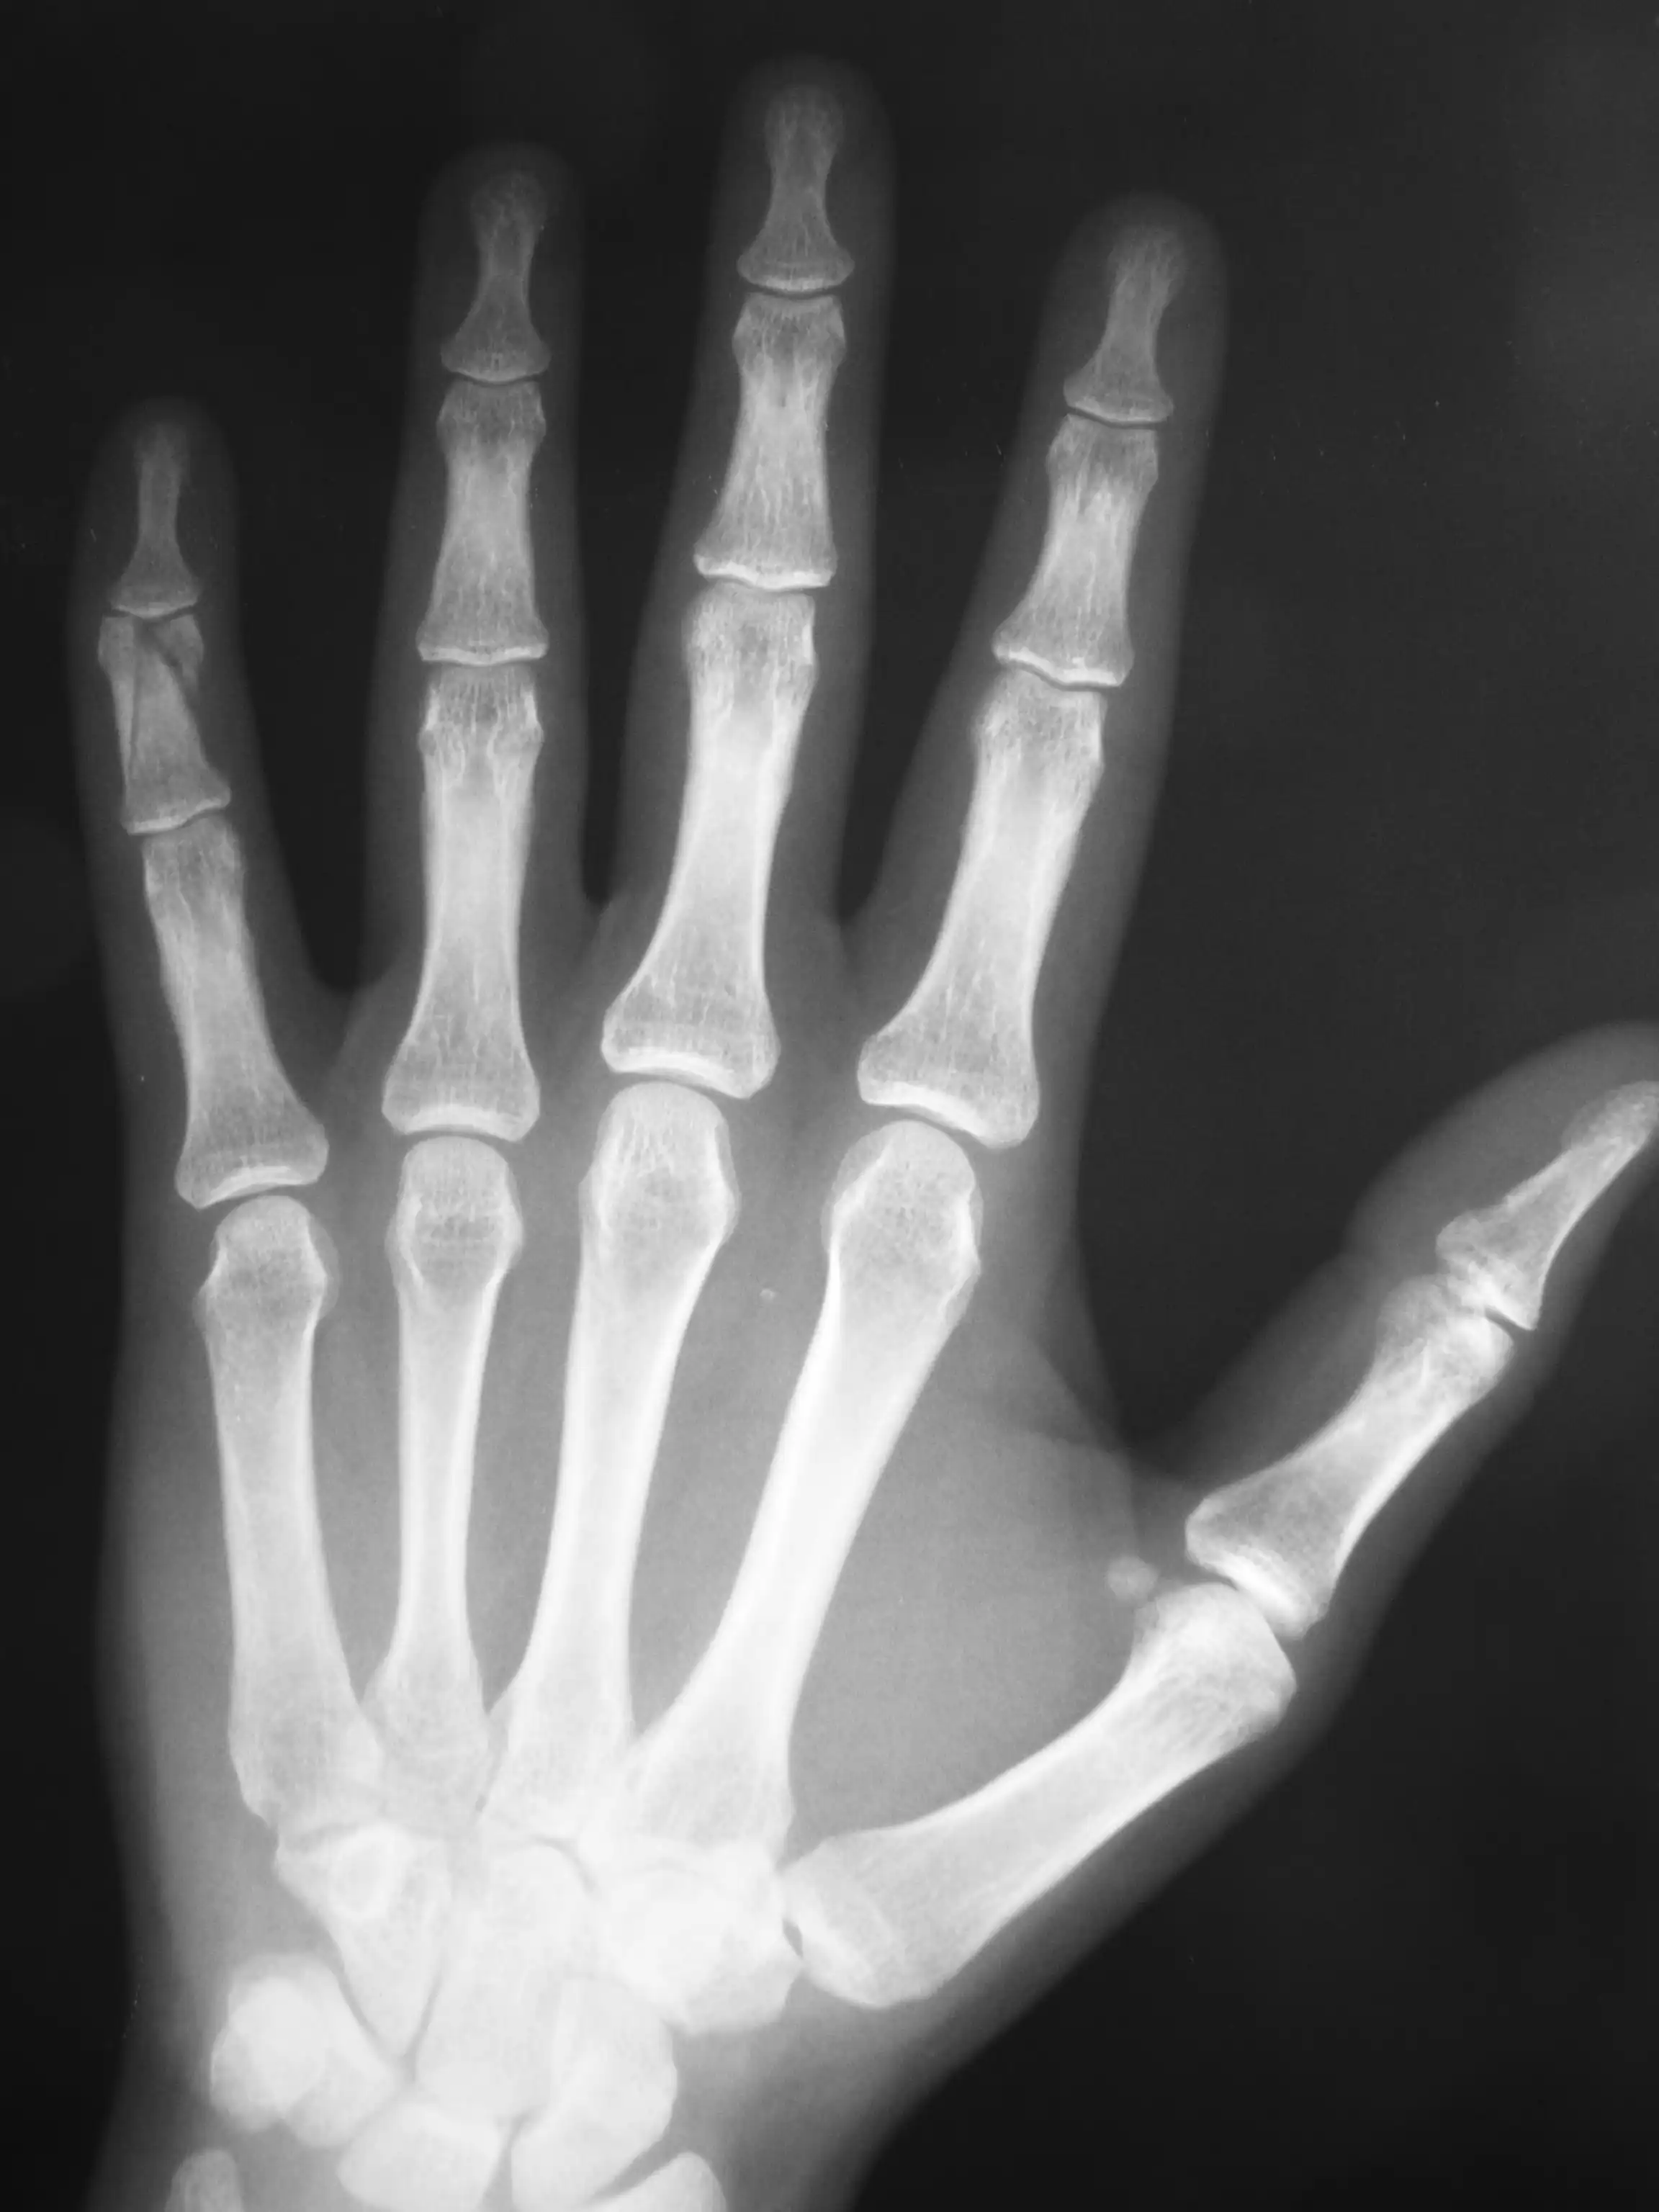

Este día se celebra cada 8 de noviembre,[9] en honor al descubrimiento de los rayos X por Wilhelm Conrad Röntgen en 1895, un evento que revolucionó la medicina moderna al permitir la visualización interna del cuerpo humano sin necesidad de cirugía. La primera celebración oficial tuvo lugar en 2012,[7] marcando el comienzo de un evento anual en el que se realizan actividades como conferencias públicas, jornadas de puertas abiertas en departamentos de radiología, y eventos mediáticos.[7][8][10]